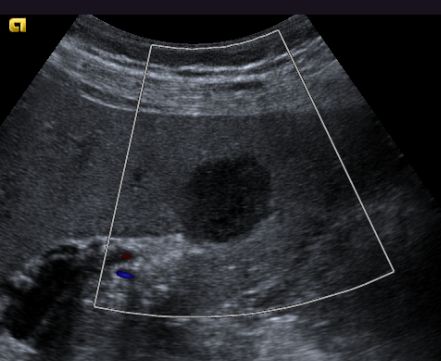

| Leber - Metastasierung | ![]() |

48-jähriger Mann mit hepatisch metastasiertem Pankreaskopf-Karzinom.

Histologische Sicherung vor 6 Monaten: schlecht differenziertes Adenokarzinom. Chemotherapie: FOLFOXIRI. Restaging: Progress. Leber mit Metastasen durchsetzt.![]() |